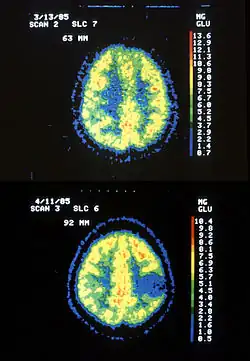

Two PET images—the upper of which shows a normal brain and the lower shows astrocytoma | |